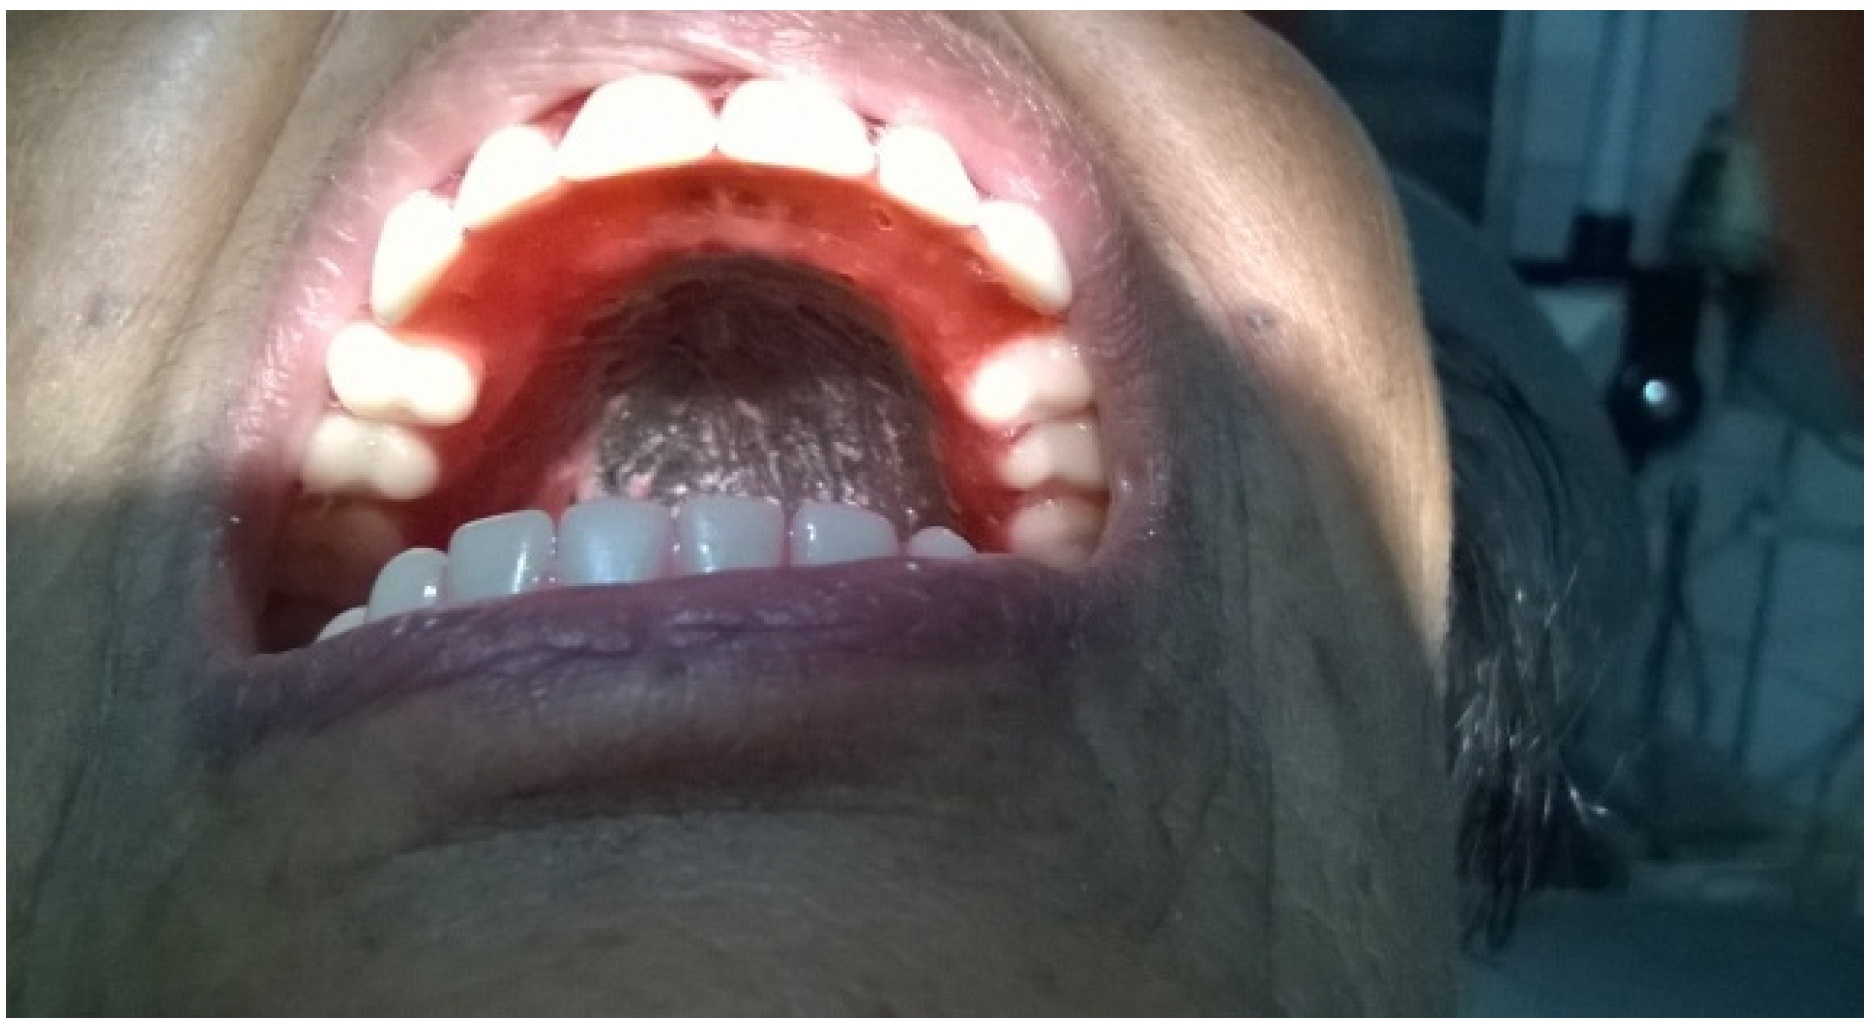

2. Case Presentation

3. Discussion